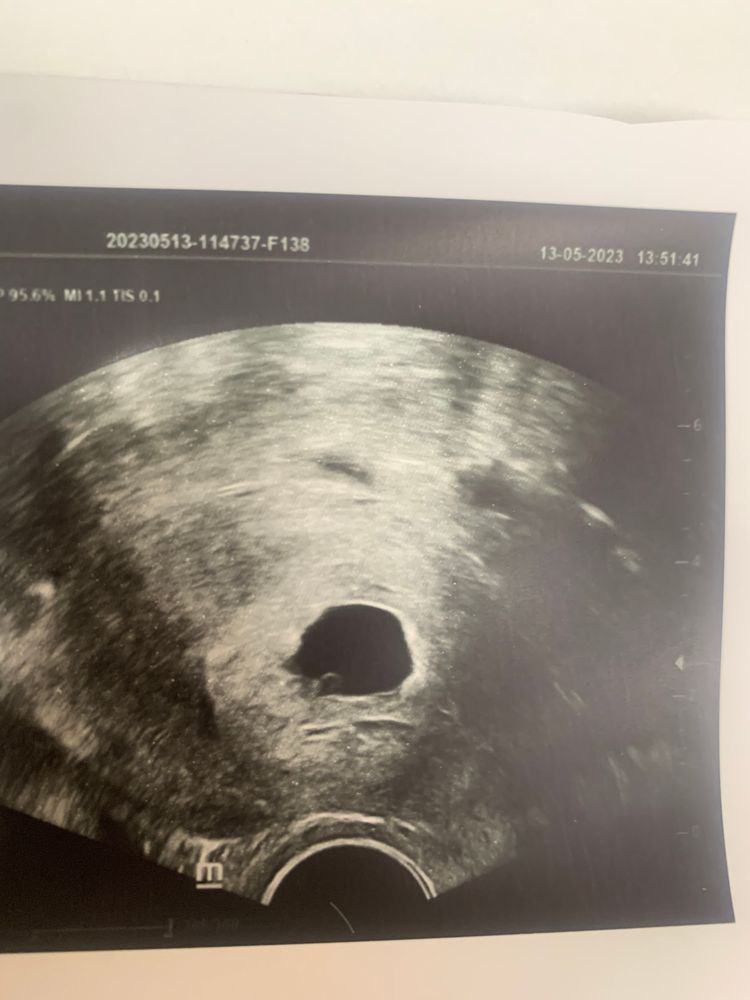

Вообще, конечно, обалдеть у тебя быстро торопыш развивается! Я щас увидела твой вопрос про мое узи (для тех, кто будет читать, уточню, у нас перенос в один день был), так вот у меня на 21 дпп увидели только плодное яйцо 5,5*4,3мм и желточный мешок 3мм 😸

Хгч после 17дпп 29 дпп УЗИ